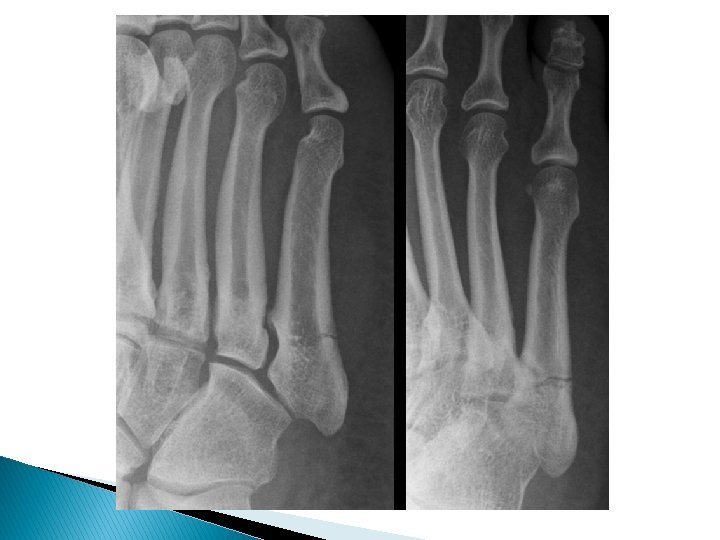

Lisfranc Injury (Tarsometatarsal fracture-dislocation �A condition characterized by disruption between the articulation of the medial cuneiform and base of the second metatarsal ◦ unifying factor is disruption of the TMT joint complex ◦ injuries can range from mild sprains to severe dislocations ◦ may take form of purely ligamentous injuries or fracture-dislocations ◦ ligamentous vs. bony injury pattern has treatment implications